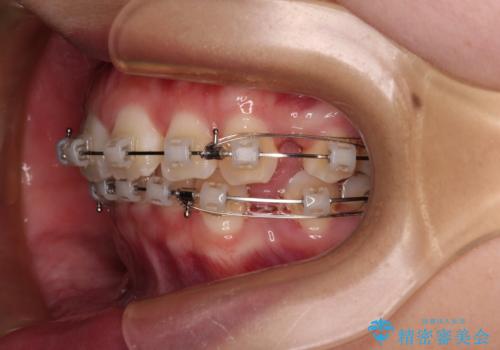

- 矯正装置

- クリアブラケット

- 前歯部のデコボコと口元が出ているのが気になるとのことで来院された患者様です。

口元の突出感の解消と、このままデコボコを解消するとさらに出っ歯傾向になってしまうことを考慮し、上下左右の小臼歯を抜歯しクリアブラケットにて矯正していくこととしました。